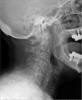

JFC Cuerpo extraño en laringe. hueso de pavo.